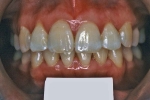

| 治療前後の比較